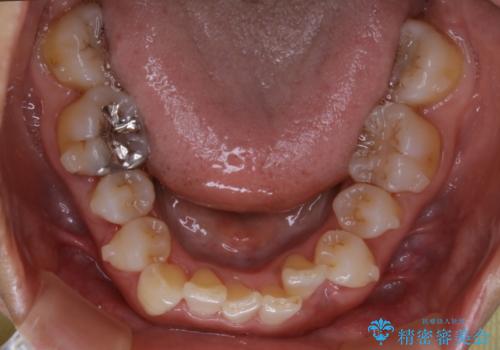

- 上下の歯のがたつきと、噛み合わせが深いことを気にされてご相談にいらした方です。噛み合わせに参加していない歯を抜歯してインビザラインにて治療を行いました。

一般的に噛み合わせの深い方へのインビザライン治療は適応が難しいとされていますが、今回は噛む力を上手にコントロールできたことと、内側に入り込んでいた前歯の角度を調整したことで下の歯がしっかり見えるようになりました。短期間で劇的に見た目が改善し、大変喜んでいただけました。